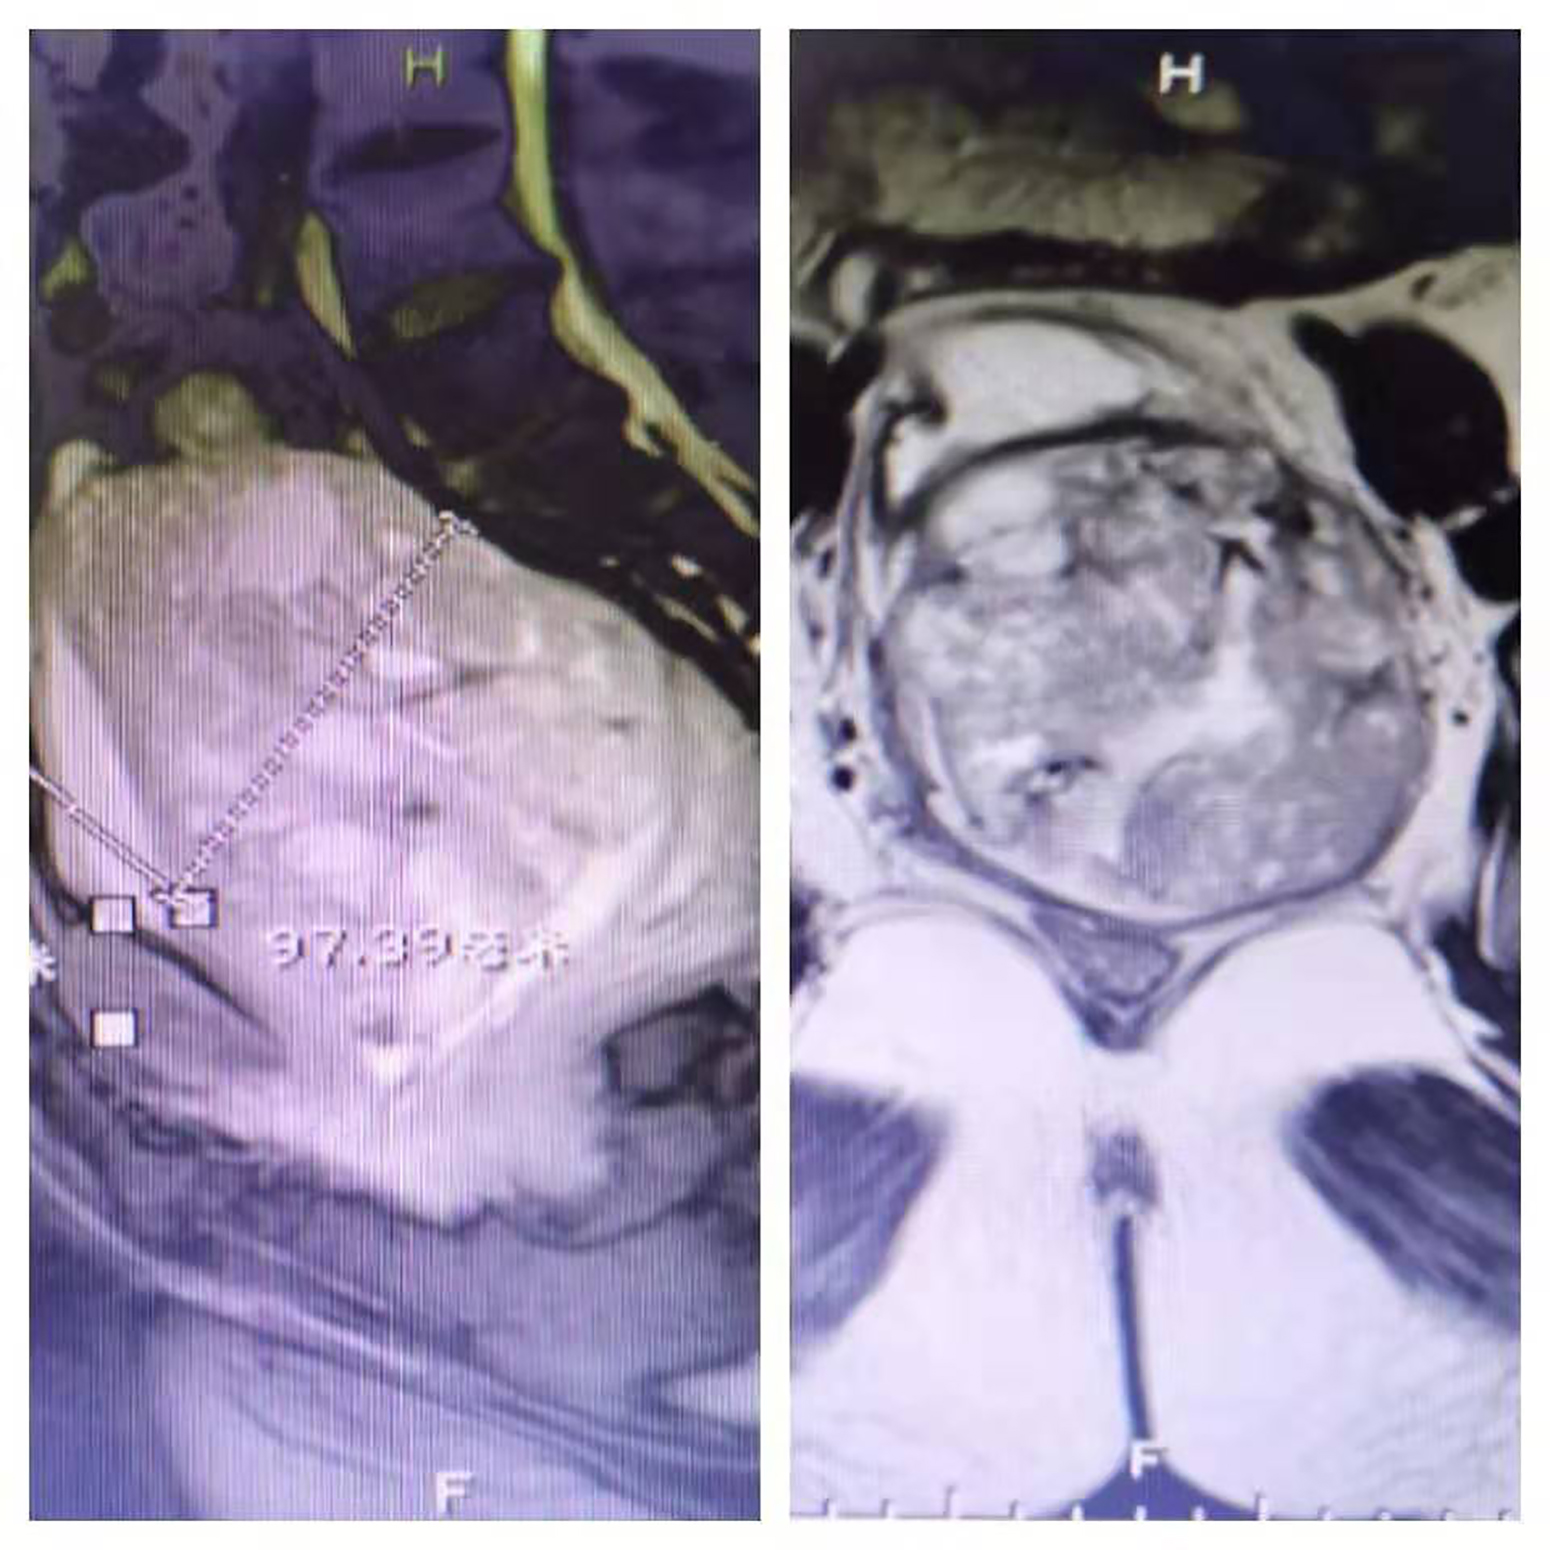

万女士紧接着说:“2019年8月5日,我们有幸被人指点说京东中美医院肿瘤二科的郑里主任‘招数’多,就急忙赶来了。见到郑里主任,她全面了解了我的病情,先行请全院多学科会诊,意见是我的体能还可以,由郑主任全面决策优化治疗方案;8月9日下午3点,为我施行了‘盆腔巨块肿瘤多支供血动脉灌注化疗术+栓塞术’,没想到肿瘤一下子就减小了很多,我的‘尿袋’也终于可以甩掉了...”

图片:患者肿瘤术前(左)和术后(右)对比